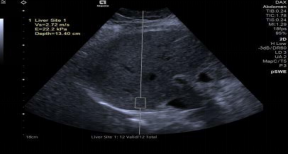

*pSWE弹性成像在测量开脏硬度时速度更快,更精确,重复性更高。